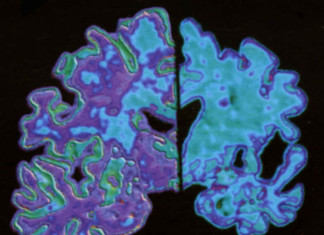

Protección «Natural» contra la enfermedad de Alzheimer

deCODE Genetics, junto con sus colegas de la compañía farmacéutica Genentech, informó hoy en la revista Nature el descubrimiento de una variante de la...